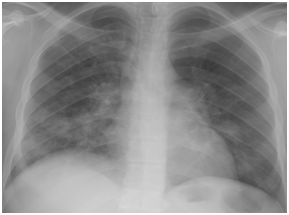

Figure 4D Follow up chest X-ray after 7 days from starting H1N1 therapy.

Figure 4 H1N1 radiological pictures in a diabetic 28-year-old transplant recipient.